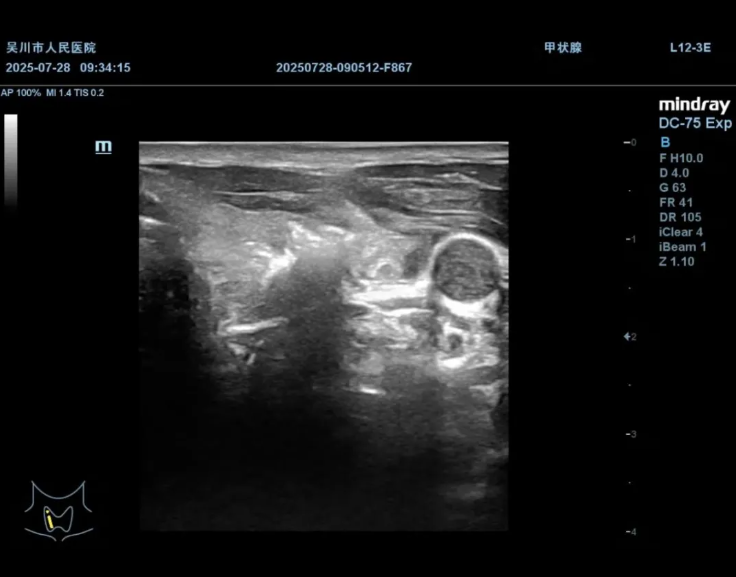

启动消融,通过高温灭活结节,实时观察结节逐渐气化

术后超声造影

明确消融范围覆盖结节,确保消融效果

手术中,刘志对手术路径规划、消融范围把控等关键环节进行了细致指导,与我院超声科陈兴华医生默契配合,在实时超声引导下精准操作,将消融针直达病灶,通过能量释放使肿瘤组织凝固坏死,实现原位灭活。整个过程患者生命体征平稳,术后仅留下微小穿刺点,恢复速度也远超传统手术,极大地减轻了患者的痛苦,患者及家属对治疗效果十分满意。